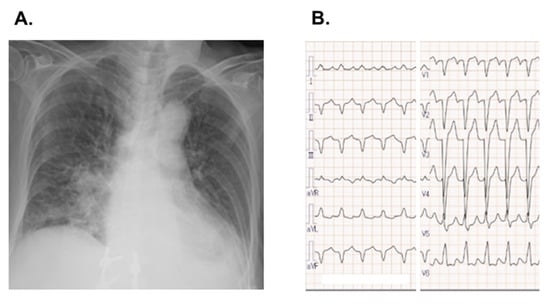

2.2. On Admission

2.3. In-Hospital Course